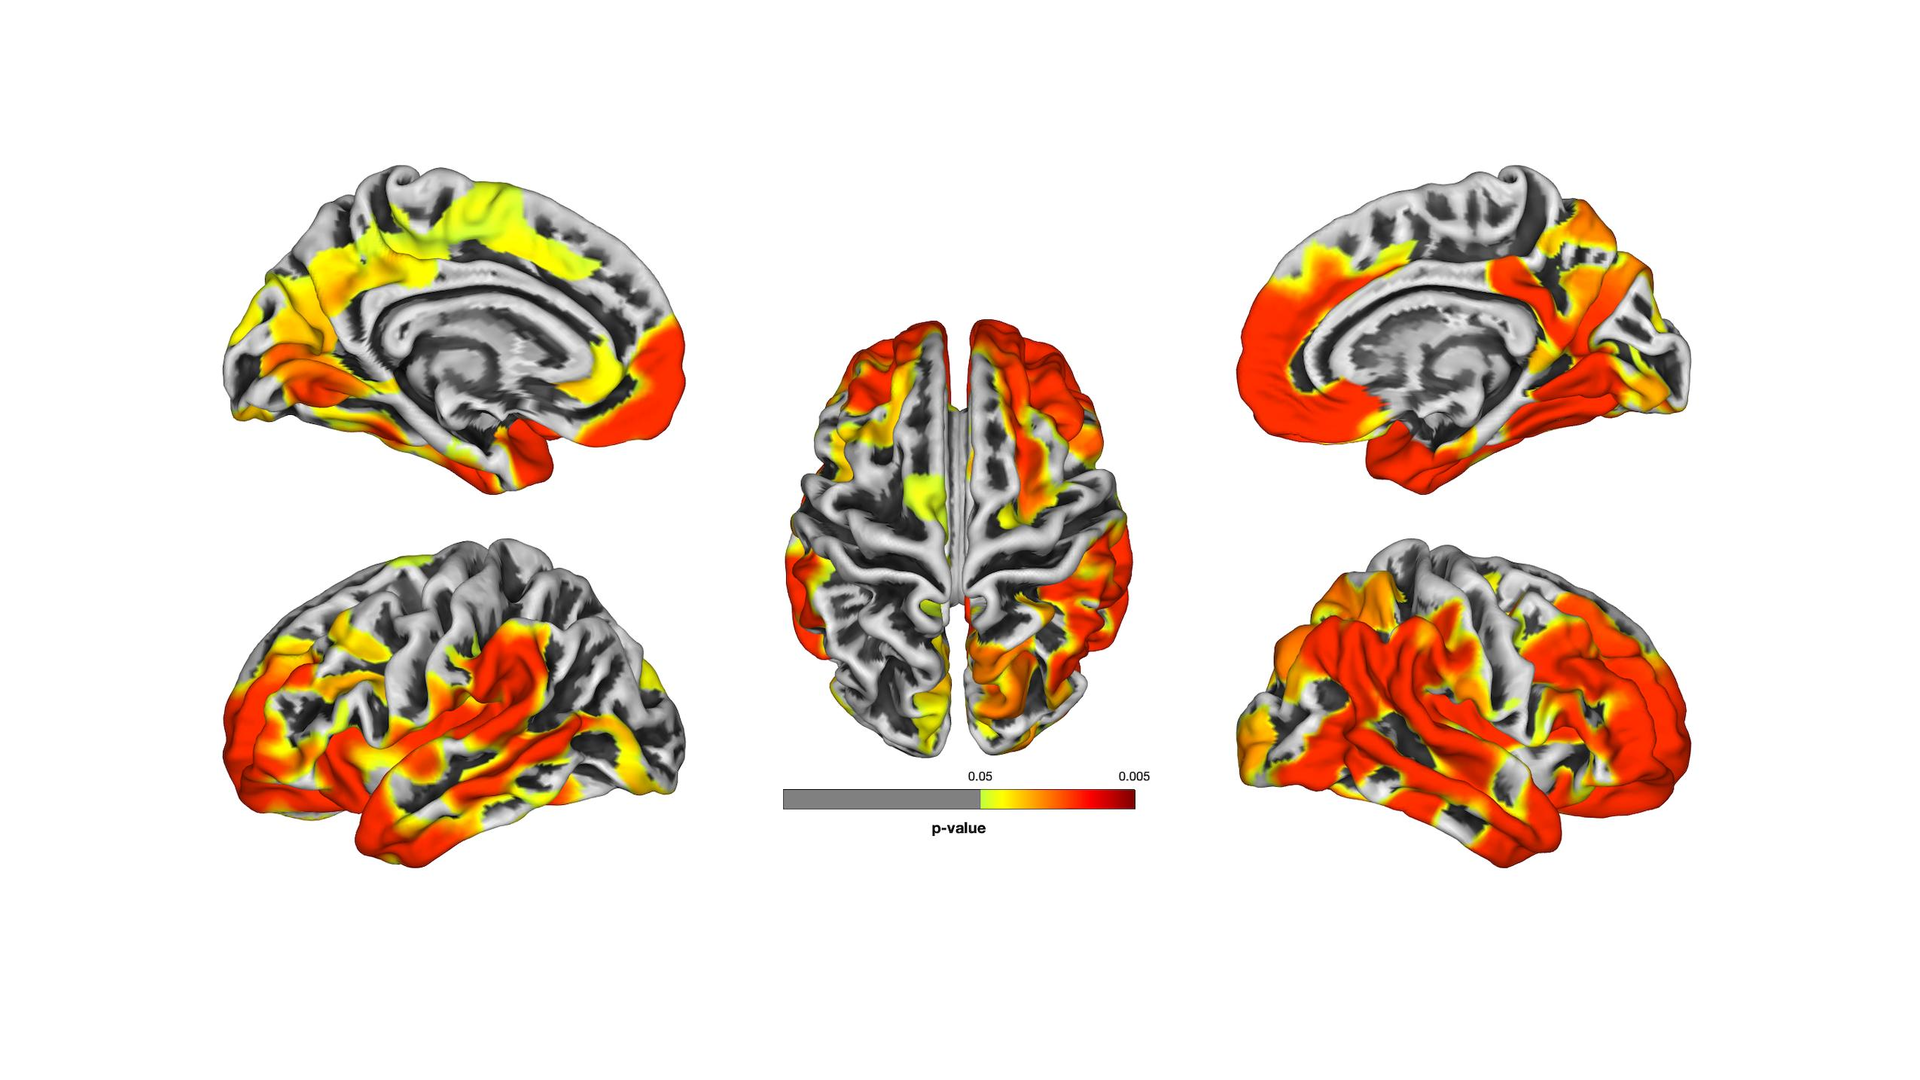

One study published in Alzheimer’s and Dementia: Diagnosis, Assessment and Disease Monitoring shows that many responders with CI have reduced gray matter thickness in the brain consistent with neurodegenerative conditions and evidence that their brain "age" is about 10 years older than the population average.

One of the studies is the first to use MRI imaging to assess the brain matter of World Trade Center responders with and without symptoms of CI. The goal was to determine if those in their midlife have developed CI due to neurotoxin exposure at Ground Zero. The ages of patients was from 45 to 65 years, a range where cortical atrophy is rare in the normal population.